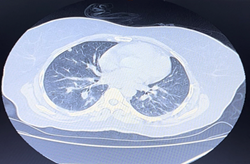

Imaging was ordered and multivisceral metastases were noted: hepatic, pulmonary and vertebral.

Figures 35: Presence of multivisceral metastases with choroidal location as the primary tumor CT-detected.

Figure 3 Vertebral metastasis.

Figure 4 Lung metastasis.

Figure 5 Hepatic metastasis.